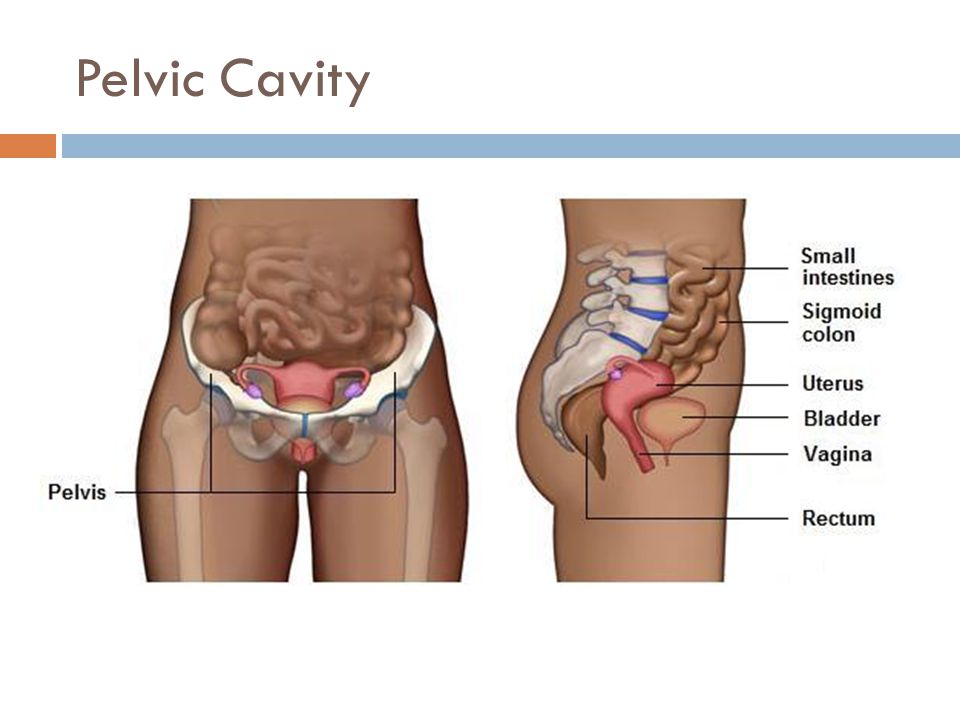

Анатомия малого таза: детальные схемы и изображения

Раздел: Образы вокруг